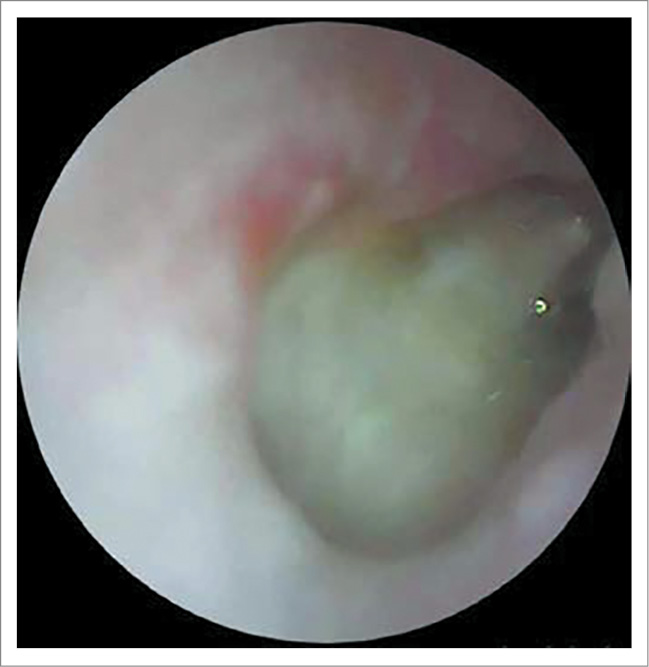

ЛОР-статус на момент поступления: AD – околоушная, заушная область не изменена, при пальпации безболезненна. При отоскопии: наружный слуховой проход несколько сужен из-за отечности стенок, в просвете визуализируется скудное гнойное отделяемое. Определяется тотальная перфорация БП, слизистая медиальной стенки барабанной полости утолщена, покрыта серо-белым субстратом (фибрин? некротические ткани?); рис. 1.

Рис. 1. Отоскопическая картина справа при поступлении: тотальная перфорация БП, слизистая медиальной стенки барабанной полости утолщена, покрыта серо-белым субстратом (фибрин? некротические ткани?).